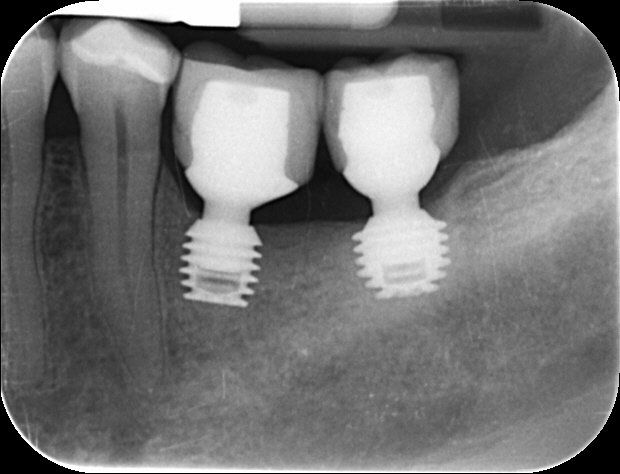

A dental implant is a medical grade titanium rod which is placed into the jaw. It is used to support one or more false teeth. In practice both the false teeth and the supporting rod are known as ‘implants’.

Before proceeding with implant treatment an examination is necessary to take impressions (to make models of your teeth) and take x-rays to assess your bone level and sometimes a cone beam (CBCT) scan especially if multiple implants are required. On the basis of this examination, a precise report, treatment plan and quotation is provided.

There are several types of restorations that can be used over an implant:

A crown

- involves one tooth only and is made of natural shade white material

A bridge

- involves three or four teeth over two implants and again is made of high strength natural shade white material.